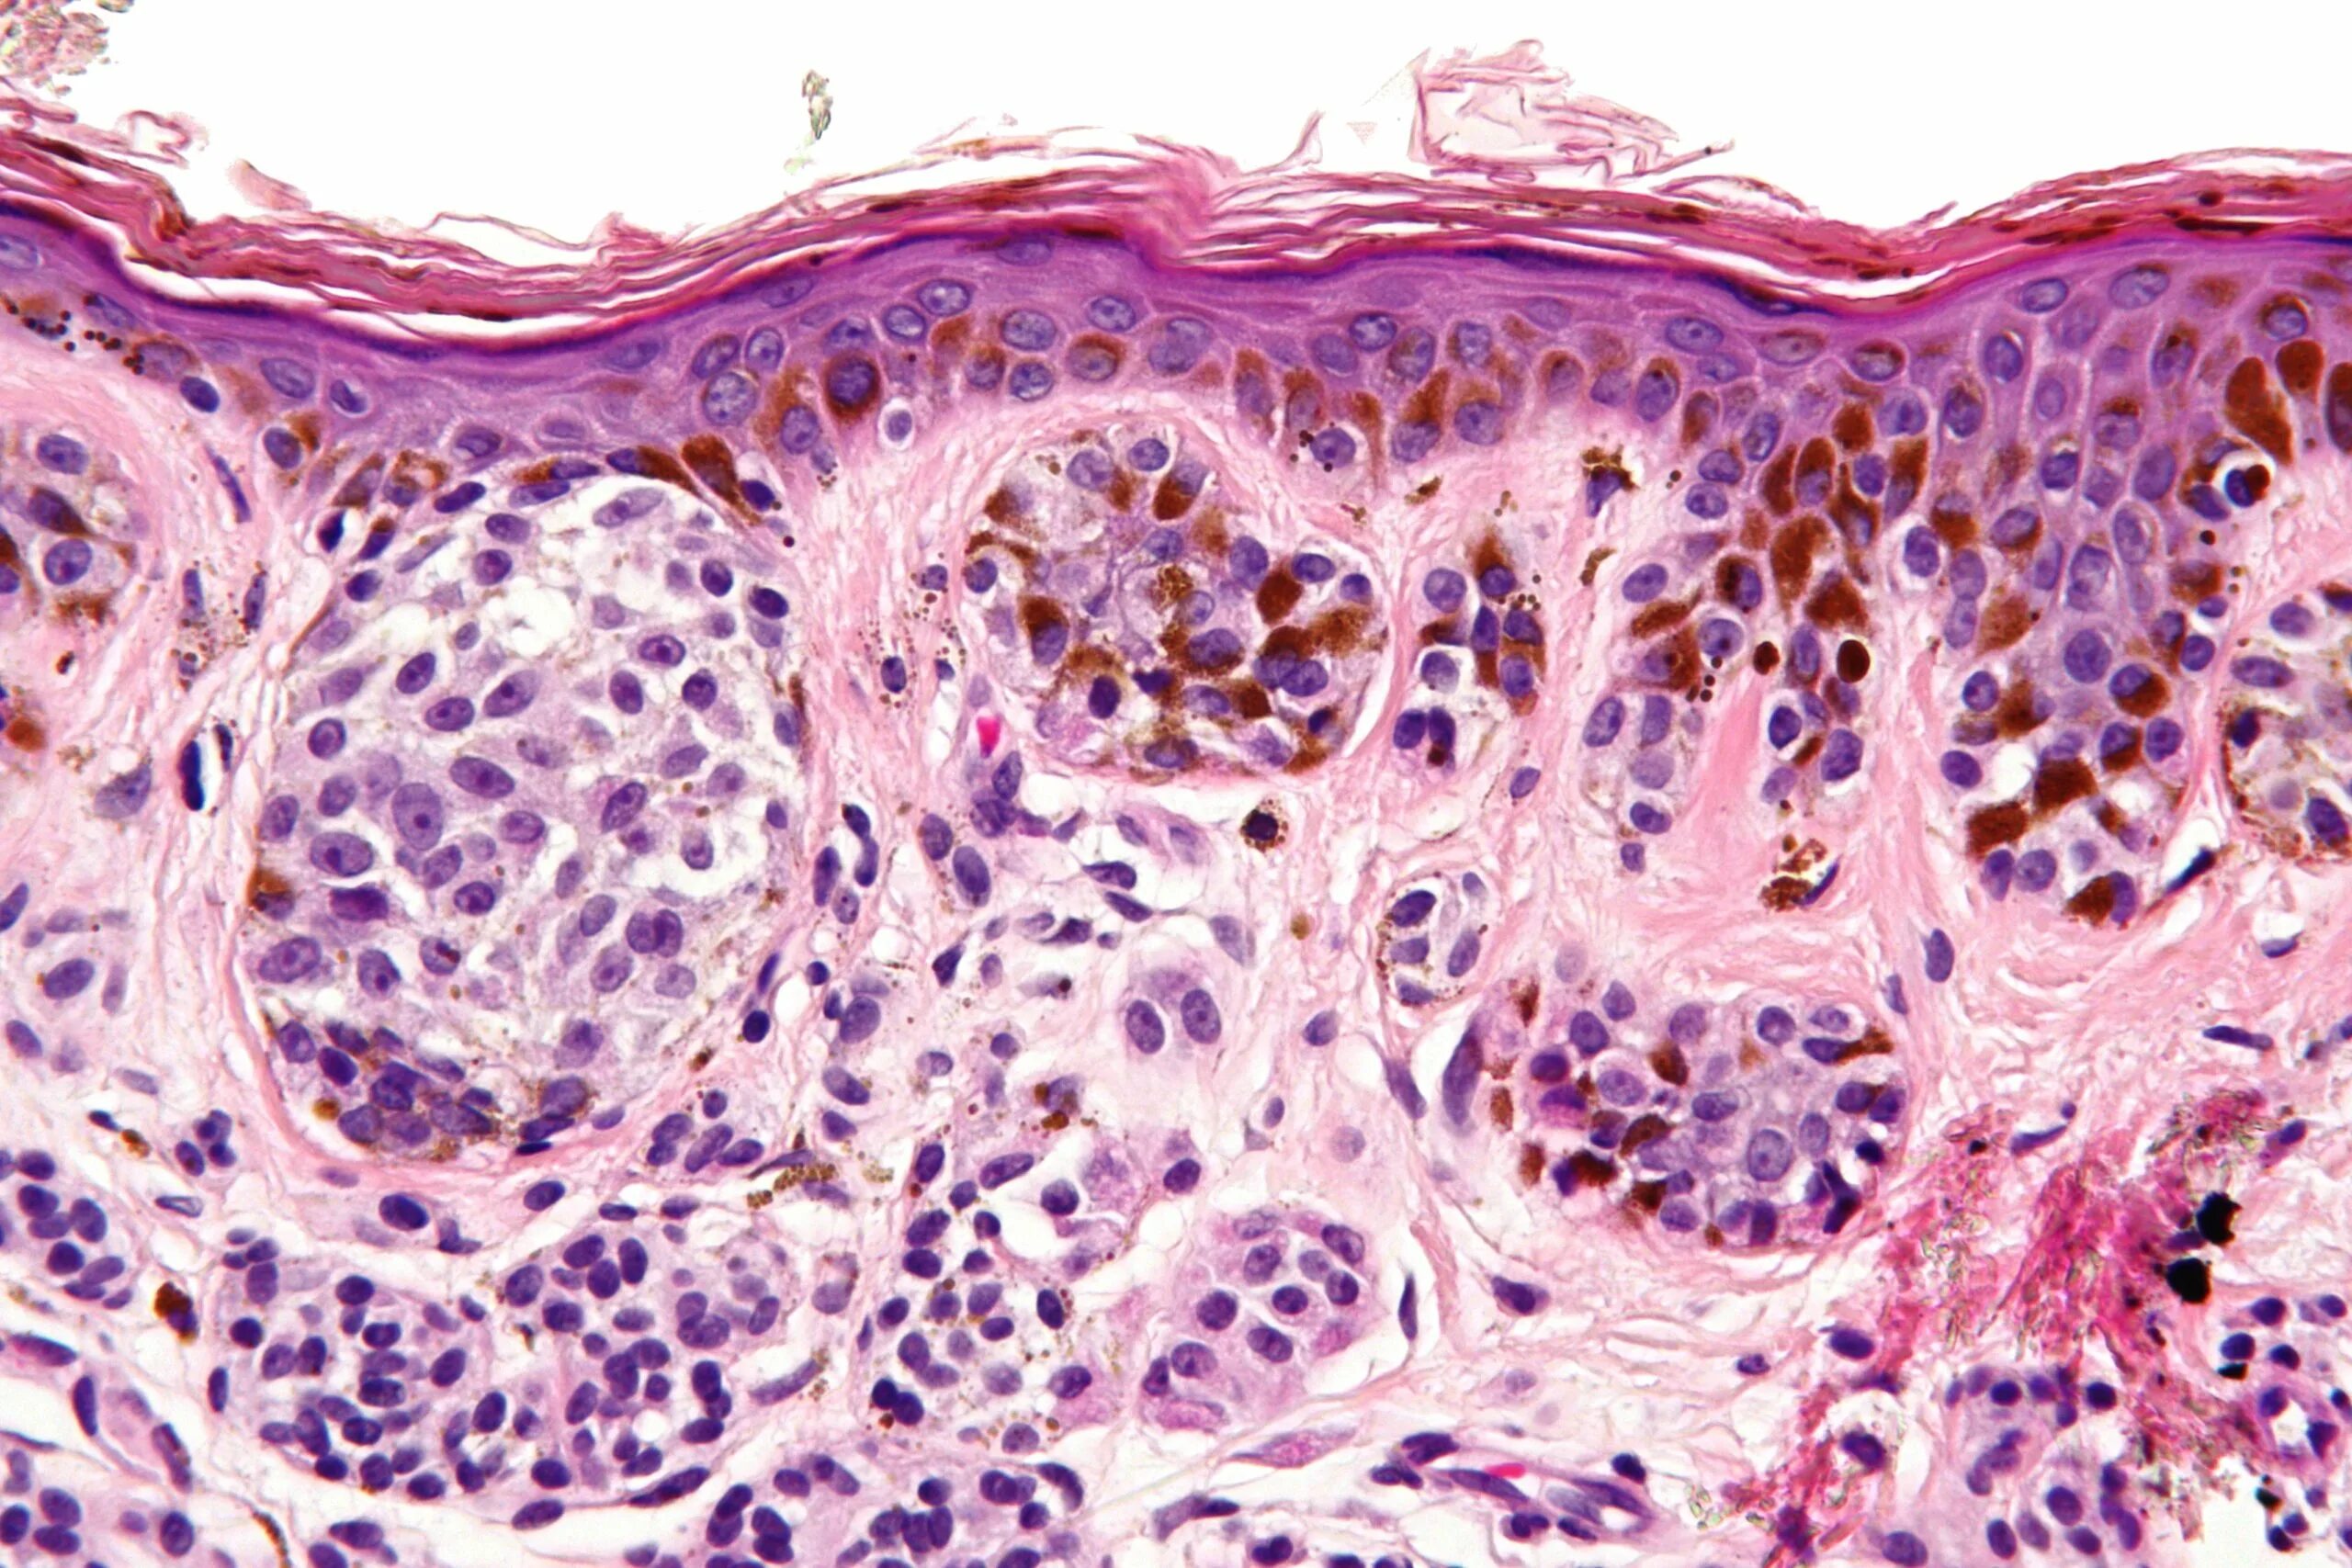

Пограничная гистология